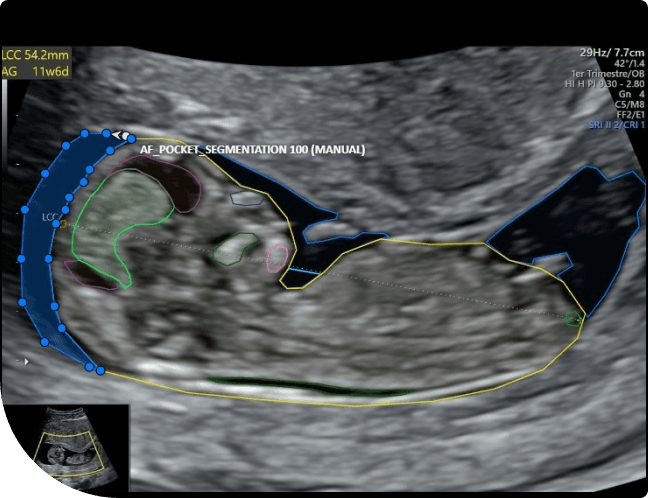

Mardi Lab collaborated with Deepecho, a leading medical technology company, on a critical annotation project focusing on identifying and labeling various fetal anatomical structures in ultrasound images. The annotation work involved using polygon, polyline, and ellipse tools to precisely outline structures such as the Myometrium, Ventricles, Choroid Plexus, Cerebellum, Cisterna Magna, Humerus, Heart, Lungs, AF Pocket, Placenta, and Spine. The project aims to create an AI model to track all the above aspects related to Fetal helping in radiologist / specific medical section to smoothen their day to day processes and analyst.

Fetal Annotation based on Fetal Anatomy Ultrasound Annotation project was designed to support radiologists in identifying key fetal anatomical structures.

Using specialized annotation tools, our team annotated each ultrasound image, focusing on clarity, boundary accuracy, and structure differentiation.

Different CVAT annotation tools were applied depending on the anatomical structure’s shape to ensure maximum precision during the Fetal Annotation Execution phase.

Polygon Tool

Used for irregular structures like the placenta and lungs.

Ellipse Tool

Used for rounded organs like ventricles and cisterna magna.